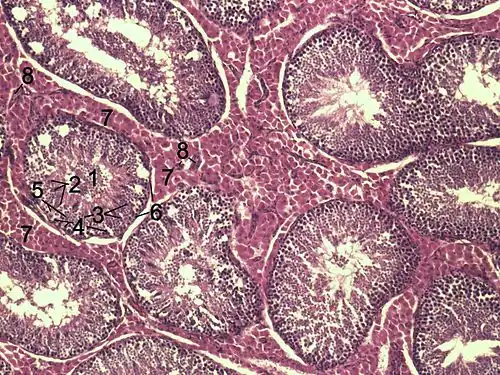

1) Lumen eines gewundenen Samenkanälchens

2) Spermatiden

3) Spermatozyten

4) Spermatogonien

5) Sertoli-Zellen

6) Myofibroblasten

7) Leydig-Zellen

8) Kapillaren